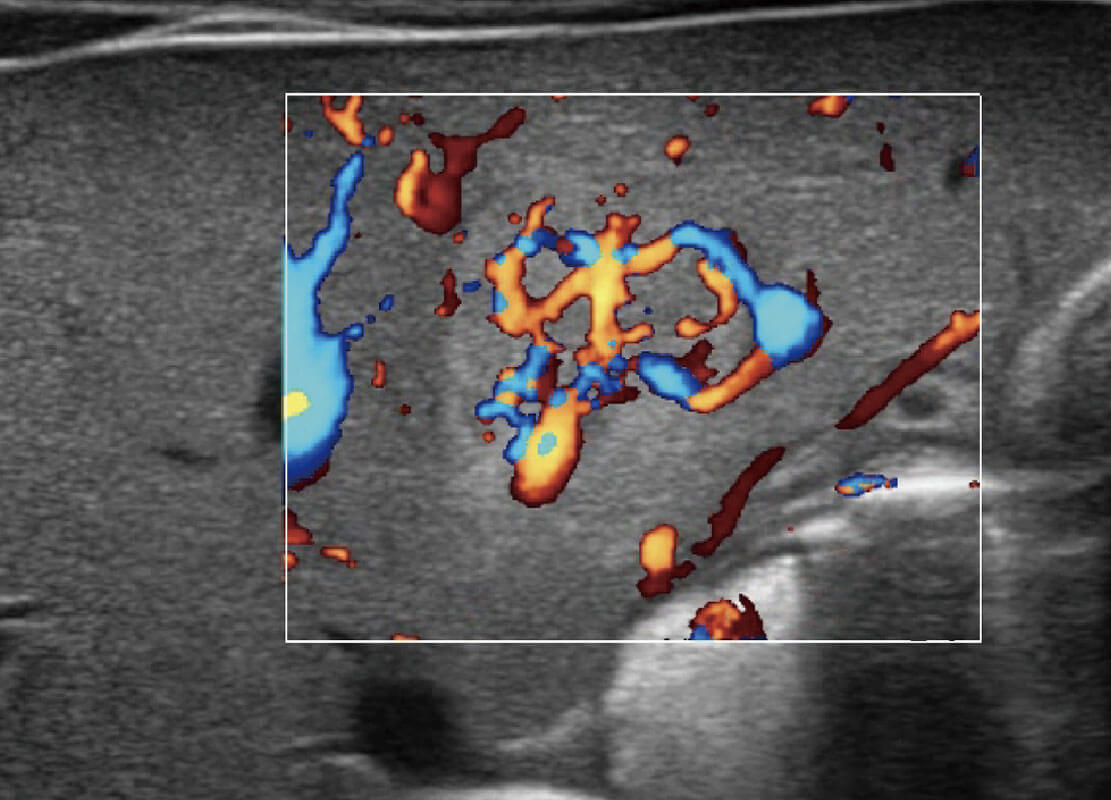

P60搭载一系列胎儿心脏成像技术,实现精细的胎儿心脏评估。

四腔切面

四腔心血流

右室双出口

胎心容积成像